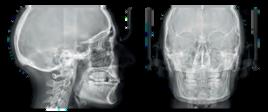

The smallest 3D/2D suspended system in the world evolves to integrate teleradiographic examinations as an extra option Innovative design, flexibility and userfriendliness. Out of our experience comes the best solution for every dentist

Thanks to lightweight, minimalist design, the wall-mounted system can be incorporated into any practice with ease, optimising space and streamlining installation without forgoing high performance Its modular, upgradeable configuration means it can be expanded as your practice grows

Hyperion X5 provides an effective response to your clinical needs with a wide range of models

From 2D digital panoramic imaging with the MultiPAN function to high-definition 3D volumetric imaging, X5 places a variety of clinical scans at your disposal, cephalometric and maxillary sinus scans included Exceptional flexibility makes it suitable for both standard and advanced scans, with the field of view adaptable to specific specialist needs.

Guided positioning via laser tracking ensures correct patient positioning, offering comfort and precision throughout every scan

The servo-controlled Scout View system - a valuable aid for precision alignment of the area of interest - displays sagittal and frontal images that are obtained with ultra-low radiation exposure. The scan area can be modified directly from the PC to obtain optimal results.